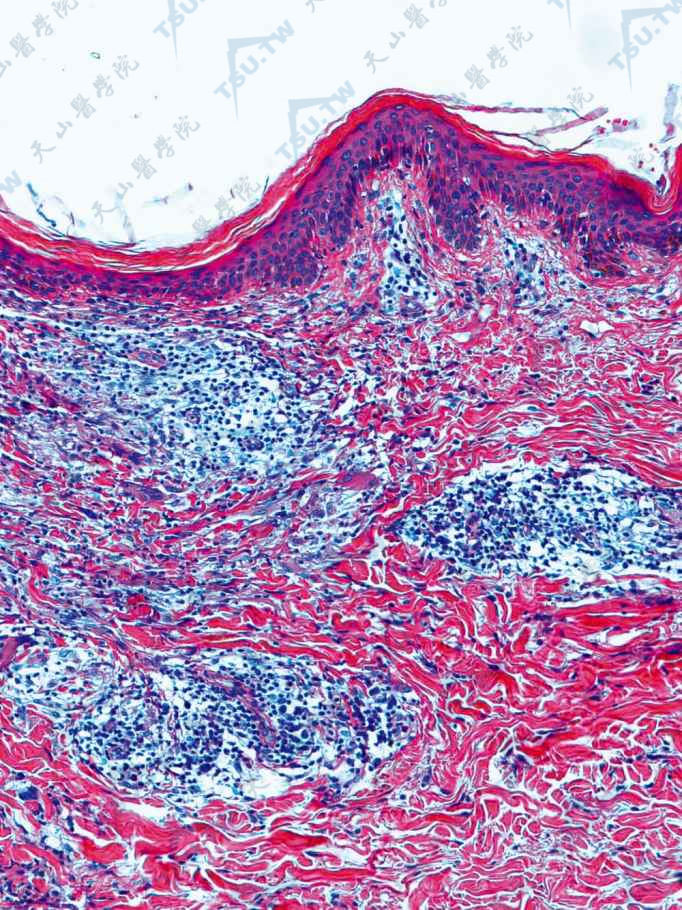

麻风是由麻风分枝杆菌引起的一种慢性传染病,主要侵犯人的皮肤和周围神经,至人残疾。1985~2000年的15年间,全球麻风发现病例数及发现率基本保持稳定,且1995年以后上升,1998年达到高峰,以后稳定在75万例左右,2005年降至29.6万例。

1麻风分枝杆菌(麻风杆菌)(mycobacterium leprae),是麻风的病原菌,系由挪威学者汉森于1873年发现。1879年德国学者奈瑟等用抗酸染色法予以确认。一、麻风杆菌的形态和染色特点:麻风皮